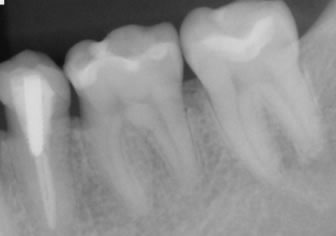

トンネリングと同様、歯の根の枝分かれした部分に歯石が付着した際の治療法です。

「ルートセパレーション」は、歯を2〜3個に分割して、歯石を清掃しやすい状態にする治療法です。最終的には分割した歯にかぶせ物をして、見た目や機能性も回復させます。

ヘミセクションは、ルートセパレーション後に残った2根のどちらかを抜歯し、最終的には歯にブリッジをして、見た目や機能性も回復させます。

トライセクションは、ルートセパレーション後に残った3根の1〜2根を抜歯し、最終的には歯にかぶせ物をして、見た目や機能性も回復させます。

ルートアンプテーションは、トライセクションの際に、歯冠を残し、歯根のみを抜歯し、最終的には歯にかぶせ物をして、見た目や機能性も回復させます。